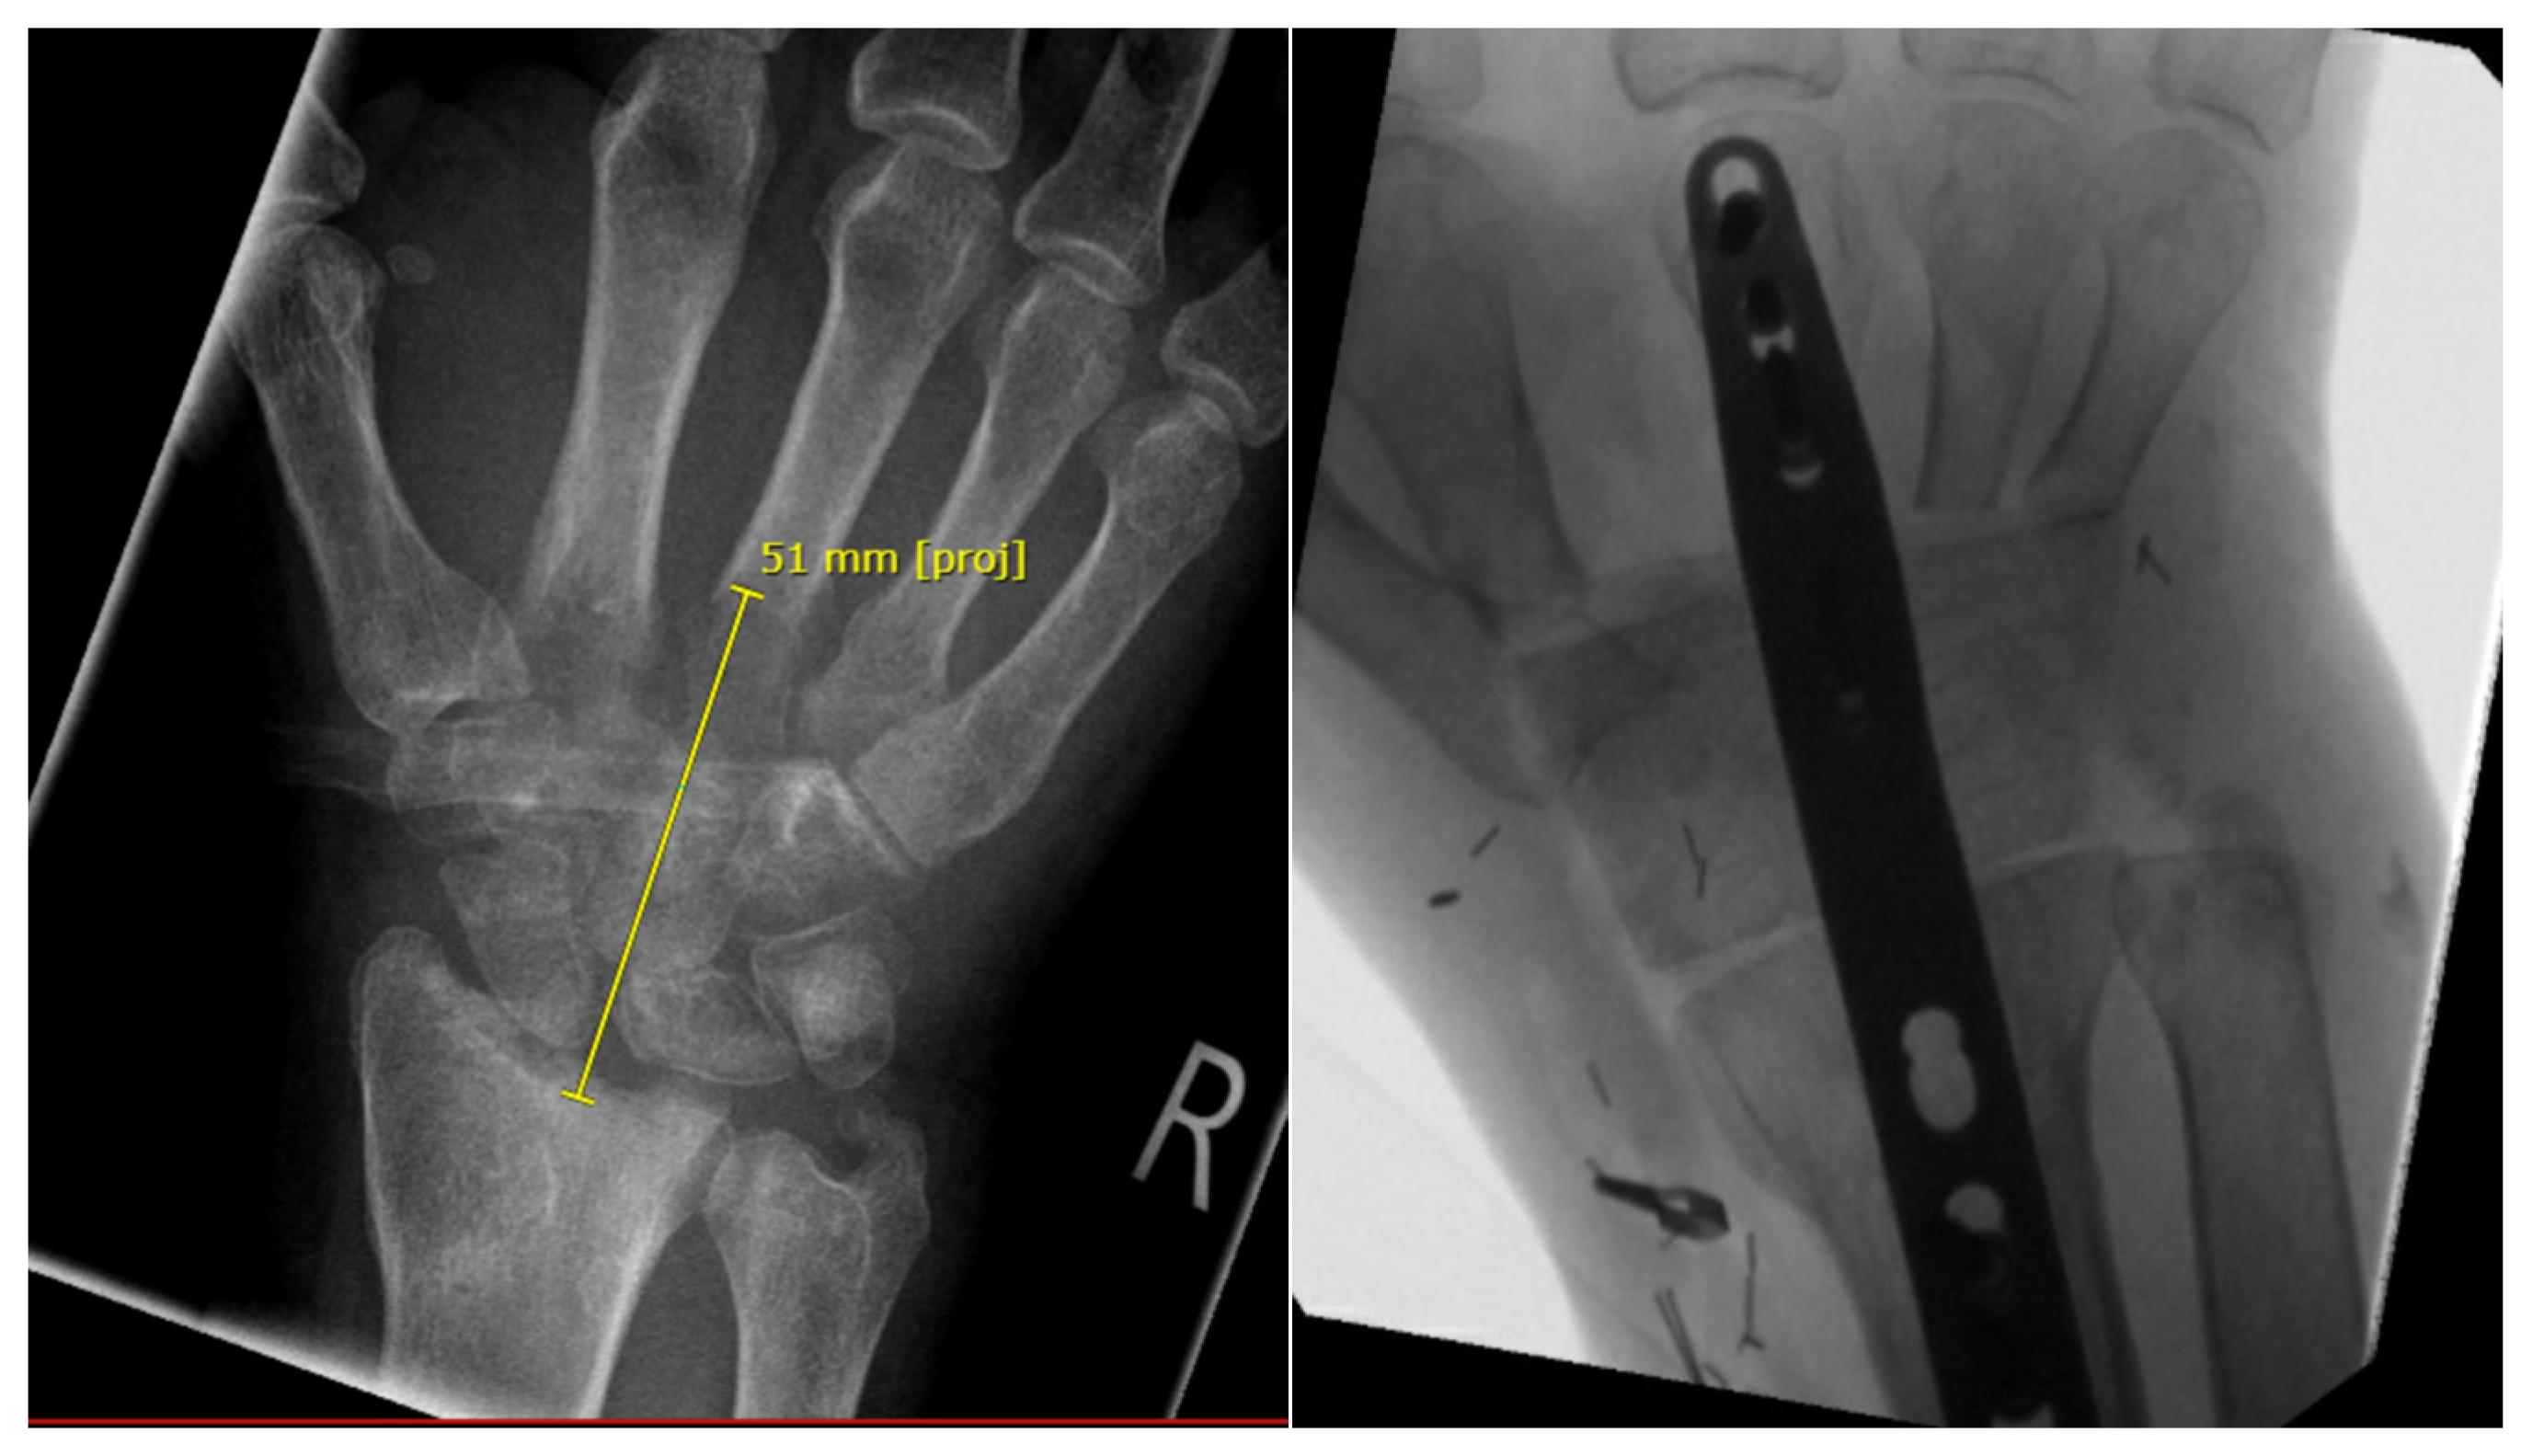

3.4. Group 4: Fusion of Scaphoid, Lunate, Fibula and Radius (RFSL-Fusion)

| GROUP 4 | Case 5 | Distal radius involving the radiocarpal surface | Sarcoma, secondary osteoblastoma | 61 | 20 | 9 | Vascularized fibula | RFSL-Fusion | N/A N/A | 25-0-30 50-0-60 | 70% | MMWS = 65 DASH = 24 | yes |